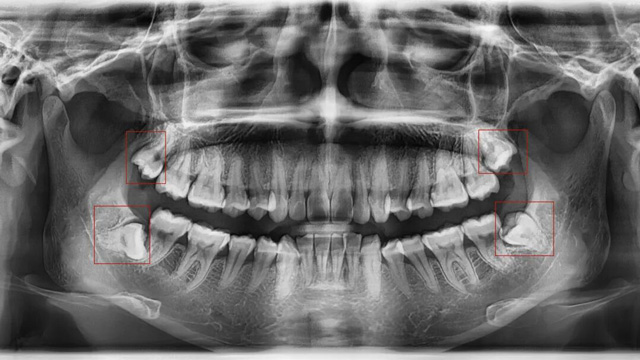

01智齿挤压邻牙,导致牙齿拥挤/移位

这是最常见的拔除原因。正畸的核心需求之一一般是“排齐拥挤牙齿”,而智齿作为口腔中最后萌出的牙齿(通常在20岁左右萌出),由于生长位置特殊、空间有限,很可能会持续挤压旁边的第二磨牙,导致第二磨牙倾斜、移位,进而引发整个牙列拥挤。

如果不拔除这颗“肇事智齿”,即使通过正畸排齐了牙齿,后期也会因为智齿的持续挤压,导致牙齿再次拥挤、反弹。

如果通过X光片发现,你的智齿已经顶到邻牙牙根,或者导致邻牙出现龋坏、牙周炎,无论是否正畸,都建议尽早拔除。

03智齿位置不正,未来存在潜在风险

有些智齿虽然目前没有疼痛、没有挤压邻牙,但拍X光片后发现,它属于“埋伏阻生”(完全埋在牙龈下),或者生长方向异常,未来很可能会萌出、挤压邻牙,甚至引发囊肿、肿瘤等问题。对于这类堪比“定时炸弹”的智齿,医生通常会建议拔除,避免后续出现更严重的口腔问题。